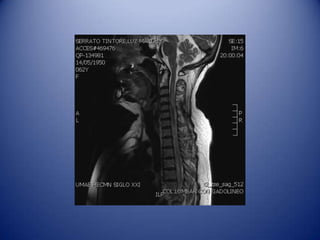

MRI: Hyper intensity with T1

enhancement, suggestive of

longitudinal myelopathy

From C2 to T12 with high activity in

Case: Female, 62years old.  2001: Optic Neuritis in right eye.  2010: Non Hodgkin lymphoma, QxTx RxRx.  May 2010: Optic Neuritis in left eye. Hypotiroidism. ANA 1:640 H, lymphopenia, leukopenia, Neurolupus: Pdn 50mg/d and Mycophenolate.  Oct 3 2010: Hyperstetic sensitive level C5 and T7, medular discharges, hyporeflexia.

• 45.

Oct 3 2010:Hyperstetic sensitive level C5 and T7, medular discharges, hyporeflexia. MRI: Hyper intensity with T1 enhancement, suggestive of longitudinal myelopathy From C2 to T12 with high activity in neuro-imaging